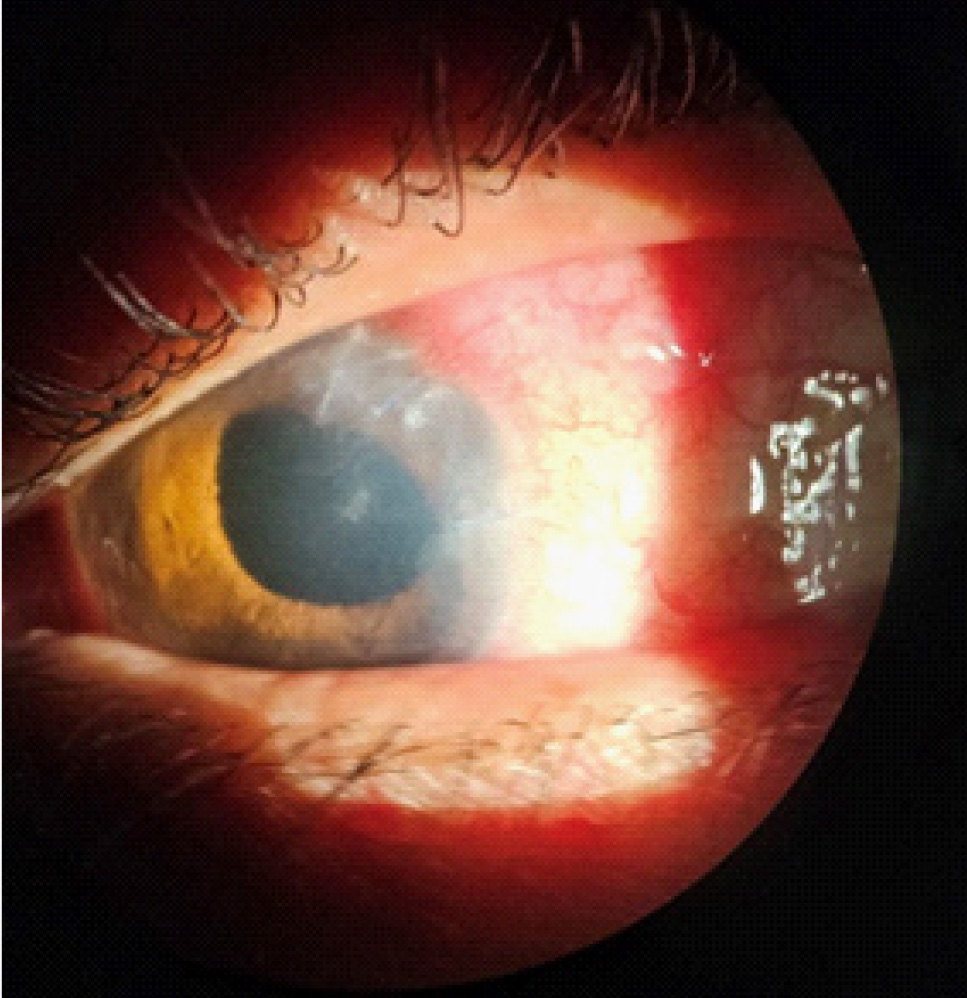

Максимально корригированная острота зрения (МКОЗ) правого глаза составляла 1.0, левого – соответствовала правильной светопроекции, пневмотонометрия OD – 19 мм рт. ст., офтальмотонус OS пальпаторно соответствовал норме. Данные биомикроскопии OD соответствовали норме. Биомикроскопия OS: отмечалась смешанная инъекция, определялись отечность роговицы и запотелость эндотелия, по меридиану 5 часов рубец, непрокрашивающийся флюоресцеином, влага передней камеры с гипопионом, в ткани радужки по меридиану 4–5 часов определялось объемное образование, реакция зрачка на свет отсутствовала (рис. 1). Визуализировалась афакия, в стекловидном теле – воспалительные клетки, детали глазного дна были трудноразличимы.

Рис. 1. Фото левого глаза на момент осмотра в приемном отделении